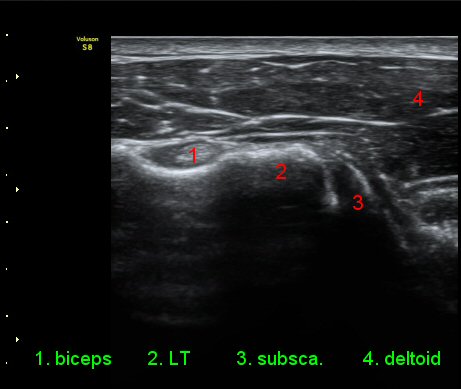

ÀÌµÎ¹Ú±Ù°Ç È¾´Ü¸é°Ë»ç¿¡¼­ °ÇÁÖÀ§¿¡ ¼Ò·®ÀÇ ¼ö¾×Àú·ù¿Í Á¡¾×³¶³» ¾×Àú·ù°¡ °üÂûµÈ´Ù(»çÁø 1, 2).